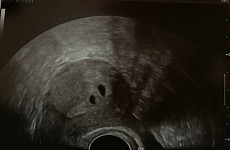

Tema besilaukiantiems dvynukų 🙂🙂

- Nėštumas